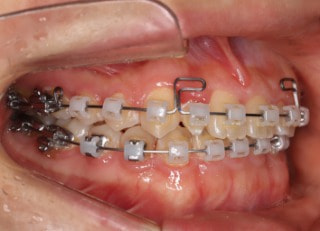

治療開始時

治療開始から25ヶ月後